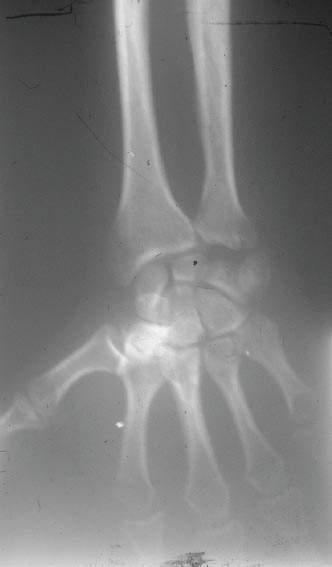

Trichorhinophalangeal syndrome type III is a newly defined clinical entity [9] inherited as an AD trait and clinically characterized by growth retardation, craniofacial abnormalities, severe brachydactyly, and sparse hair. The absence of mental retardation and cartilaginous exostoses is required for the diagnosis of type III. Other associated abnormalities include short stature, a thin upper lip and prominent lower lip, a pear-shaped nose, stubby fingers and toes with cone-shaped epiphyses, and sparse scalp hair (Figures 2.4 through 2.6).

FIGURE 2.5 Radiography reveals cone epiphysis of first phalanges and shortening of some metatarsi.